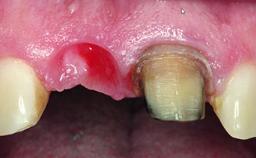

A 28-year-old patient presented at her general dentist’s office and complained about the appearance of her tooth 21. The patient had a history of trauma to this tooth. Endodontic treatment had been performed in the past and a crown placed on the tooth. A procedure to replace the old crown was performed by her dentist; however, a perforation on the middle third of the root occurred, and extraction of tooth 21 was suggested. Upon clinical and radiographic examination of the patient, who had been referred to us, replacement of tooth 21 by a dental implant appeared to be indicated.

Placement Protocol Early or late implant placement

Bone Volume Deficient horizontally, allowing simultaneous augumentation